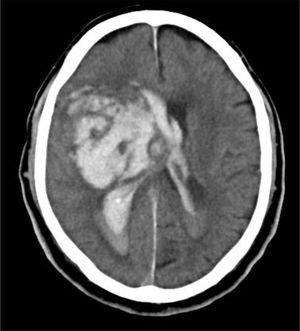

En la práctica clínica, antes de establecer un pronóstico definitivo, se recomienda la opinión de un equipo multidisciplinar experto, que minimice el sesgo personal; en esta valoración el especialista en Medicina Intensiva, por sus conocimientos sobre la enfermedad neurocrítica, juega un papel primordial. La lesión cerebral catastrófica condiciona una elevada presión intracraneal (PIC), con una disminución de la presión de perfusión cerebral e instauración progresiva de la parada circulatoria cerebral. La probabilidad de evolucionar a ME ha de sustentarse en datos clínicos, de neuromonitorización y resultados de la tomografía computarizada (TC) craneal. En primer lugar, hay que tener en cuenta la situación clínica neurológica, medida por las escalas habituales de gravedad según las diferentes enfermedades (escalas de Glasgow [GCS], Hunt y Hess, NIHSS), así como la ausencia de algunos reflejos de tronco del encéfalo. Las escalas de gravedad realizadas en las primeras horas de la lesión tienen sus limitaciones y su valor pronóstico mejora cuando se realizan después de la reanimación del paciente. La probabilidad de error pronóstico es siempre menor cuando estas escalas tienen un valor extremo; a mayor gravedad clínica, mayor probabilidad de evolución a ME37. En este sentido, algunos estudios encuentran que la abolición de 3 reflejos de tronco al ingreso es la variable que más predice la evolución a ME38. Otro de los factores pronósticos que pueden ayudar a predecir una alta probabilidad de evolución a ME es la TC craneal, ya que permite documentar el tipo, el volumen, la localización y la gravedad de la lesión estructural, así como la existencia de signos de hipertensión intracraneal y herniación cerebral. En las hemorragias cerebrales, el volumen del hematoma es uno de los predictores más potentes de evolución a ME y algunos autores encuentran que un volumen superior a 65cc es un factor determinante39. Igualmente, la presencia del «signo del remolino» en la TC sin contraste y del spot sign en la angio-TC nos indica que hay presencia de sangrado activo por arteriolas o vénulas y es un signo de mal pronóstico que algunos autores asocian con una mayor probabilidad de evolución a ME38,40,41. El desplazamiento de la línea media nos informa del grado de compresión y es un indicador, junto con el estado de las cisternas de la base, del compromiso de las estructuras encefálicas. El borramiento parcial o total de las cisternas de la base es un fuerte indicador de probable evolución a ME42. La presencia de signos de herniación cerebral en la TC implica hipertensión intracraneal y, por lo tanto, riesgo elevado de enclavamiento cerebral. Los 3 tipos más frecuentes de herniación cerebral son: herniación subfalcial, que se caracteriza por un desplazamiento de la línea media y compresión del ventrículo lateral ipsilateral (fig. 1), la herniación uncal o transtentorial, donde existe una dilatación de la cisterna del ángulo pontocerebeloso ipsilateral y del cuerno temporal del ventrículo lateral contralateral (fig. 2), y la herniación amigdalina, que se caracteriza por la desaparición de la cisterna magna y el descenso de las amígdalas cerebelosas por debajo de la línea de Chamberlain. La vaina del nervio óptico se continúa con las meninges del sistema nervioso central y acumula líquido cefalorraquídeo en este espacio subaracnoideo, aumentando su diámetro cuando hay un incremento de la PIC. Su diámetro se puede medir por ultrasonidos, resonancia magnética y TC craneal, y aunque no existe unanimidad sobre el lugar de la medición ni el diámetro necesario para considerar hipertensión intracraneal, algunos autores confirman que un diámetro de la vaina del nervio óptico>5-6mm tiene una fuerte correlación con una PIC superior a 20mmHg43,44.

Caso 1Varón de 76 años con HTA, sin otros antecedentes de interés. Deterioro brusco del nivel de consciencia en su domicilio con un GSC de 4 (O1, V1, M2). Se activa código ictus y es intubado por el servicio de emergencias extrahospitalario. Al ingreso en el hospital, la TC craneal muestra hemorragia masiva de ganglios de la base izquierdos abierta a ventrículos, importante edema cerebral y signos de herniación cerebral (fig. 4). Valorado por el Servicio de Neurocirugía y UCI, ante la situación clínica y los hallazgos de la TC craneal, se descarta cualquier tipo de tratamiento. No existe documento de voluntades anticipadas. Se informa a la familia y se realiza la entrevista previa en el Servicio de Urgencias, aceptando el ingreso en la UCI con la exclusiva finalidad de la donación de órganos. Evolución a ME en 28h, siendo donante de hígado. El receptor hepático presentó buena evolución, siendo dado de alta de la UCI en el cuarto día postrasplante.